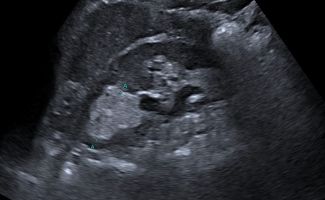

Με Υπερηχογράφημα Άνω Κοιλίας και την Ελαστογραφία ελέγχονται εστιακές ή διάχυτες αλλοιώσεις στα συμπαγή όργανα, όπως το ήπαρ, οι νεφροί και το πάγκρεας. Η διάγνωση περιλαμβάνει:

- Κυστικές αλλοιώσεις (κύστεις σε ήπαρ, νεφρούς, πάγκρεας)

- Συμπαγείς βλάβες όπως αιμαγγειώματα, αιμαγγειωμυολιπώματα, ή νεοπλάσματα στο ήπαρ, τους νεφρούς, και το πάγκρεας